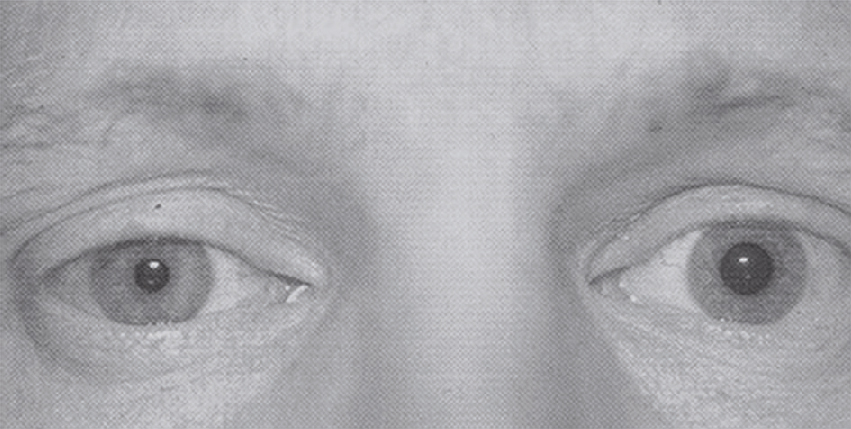

Question 12 – QRM

La patiente est perdue de vue. Elle consulte 3 ans après pour un nouvel épisode de diplopie. L’examen clinique est montré sur l’image suivante (fig. 31.2).

L'image montre une vue rapprochée des yeux humains, permettant de distinguer plusieurs parties importantes. L'iris est la partie colorée de l'œil qui contrôle la quantité de lumière entrant dans l'œil en ajustant la taille de la pupille, l'ouverture centrale noire. La pupille se dilate ou se contracte en fonction de la lumière ambiante pour protéger la rétine et optimiser la vision. La sclère, la couche externe blanche de l'œil, protège le globe oculaire et offre une structure. Les vaisseaux sanguins sont visibles à la surface de la sclère, fournissant des nutriments essentiels à l'œil. Autour de l'iris, on peut également voir la cornée, une fine couche transparente qui aide à focaliser la lumière sur la rétine. Les détails anatomiques visibles sur cette image sont cruciaux pour comprendre comment l'œil fonctionne et maintient une vision claire. Ces informations sont essentielles pour l'éducation sur la santé oculaire, car elles montrent comment les différentes parties de l'œil travaillent ensemble pour permettre la vision. Les yeux sont des organes complexes qui transforment la lumière en signaux électriques, envoyés ensuite au cerveau pour interprétation. En examinant de près ces structures, on peut mieux comprendre les processus visuels et l'importance de chaque composant dans le maintien de la vue.

Quelle est votre analyse sémiologique ?

- A reflets cornéens centrés en position primaire

- B limitation de l’abduction de l’œil droit

- C limitation de l’adduction de l’œil gauche

- D limitation de l’adduction de l’œil droit

- E limitation de l’abduction de l’œil gauche